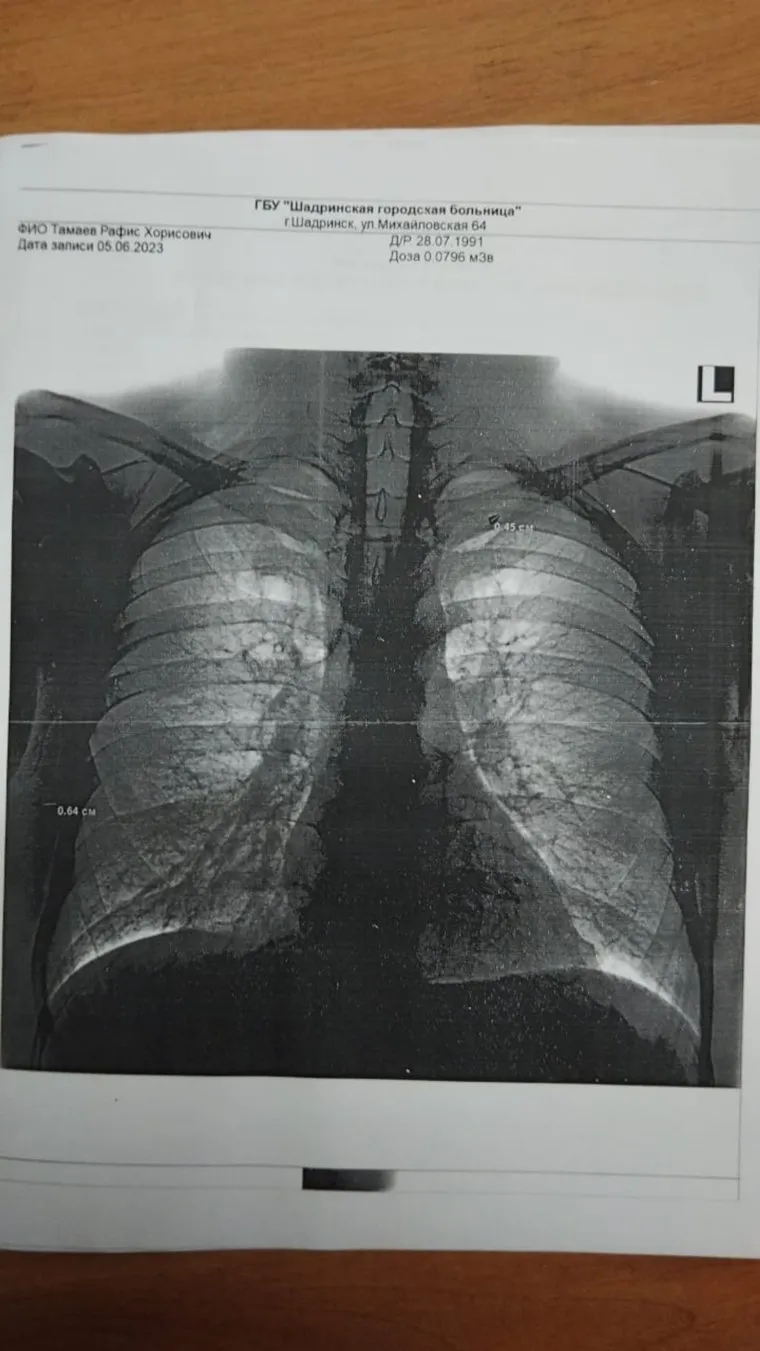

«Я был мобилизован в сентябре 2022 года. С декабря 2022 служил на территории ДНР. Был командиром штурмовиков. 16 апреля получил осколочные ранения польским снарядом возле Бахмута. Сам ездил в Донецк, сделал рентген, на котором было видно три осколка в спине: возле легкого, в нескольких сантиметрах от ребер, в плече. Сослуживцы помогали — заклеивали раны, чтобы не попала грязь, не загноились», — рассказал Тамаев.

Боец из Каргапольского округа получил осколочные ранения от польского снаряда в ДНР. На снимке видны два осколка, застрявшие в спине. Еще один осколок застрял в плече.